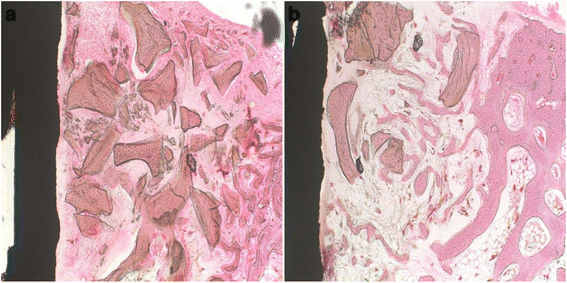

摘要:富含血小板血浆(PRP)修复因子与生物材料联合应用具有前瞻性价值。牛源性已被确定能为骨传导和骨移植材料提供生物相容性。在许多牙科和口腔外科手术中,PRP已经成为一种有助于促进愈合的有价值的辅助剂。然而,关于PRP再生能力及其在骨移植中应用的实际问题仍存在争议。本研究旨在探讨PRP联合异种骨移植修复种植体周围骨缺损的效果。方法:本实验采用12只家兔,同时进行种植体植入手术。在外科手术之前,制备自体PRP。每只兔胫骨制造一个骨缺损(直径7毫米和深3毫米)。24个钛牙种植体(直径3毫米,长8.5毫米)插入这些截骨部位。因此,在周围的骨壁和种植体表面之间形成了标准的间隙(4毫米)。治疗空隙为单纯移植组(对照组)或异种移植联合PRP(实验组)。给药治疗1, 2, 3、4, 5、6周后,用过量氯化钾溶液处死家兔。每次处死2只兔,采集牙种植体及周围骨标本进行组织学分析。结果:对照组发现新形成的骨和更好的骨愈合过程。定量分析显示,对照组的骨植入物接触的平均百分比显著高于实验组。结论:结果表明,PRP在牛异种骨移植修复种植体周围骨缺损中,PRP可能延缓种植体骨愈合。关键词:骨愈合 牙种植体 富血小板血浆 异种移植 兔背景:使用牙种植体已成为现代牙科治疗的一个重要组成部分。建议立即植入新鲜拔牙窝作为减少骨丢失和缩短假体治疗时间的一种手段。然而,残留的骨缺损,种植体颈部和残余骨壁之间,可能引起细胞迁移从结缔组织和上皮组织到缺损区,可防止材料与骨整合。对于这种缺陷,需要增加骨植入术和植入物植入。需要寻找替代骨来减少或避免自体骨移植。几种材料,从其他物种的骨骼结构(异种移植)中综合衍生或加工,已被用来替代自体骨。牛源性异种骨由于来源丰富,易于移植,被广泛用作骨移植材料。它可以提供骨传导支架,其具有与人体骨相当的矿物质含量,使之能与宿主骨结合。这是迄今为止最好的骨替代材料,引导骨再生结合使用。数年来,富血小板血浆(PRP)被认为能促进骨愈合,特别是与PRP混合的骨移植材料已被报道能增强骨形成。PRP与自体骨移植复合可提高成骨率,并能促进骨形成。最近,PRP已成为许多牙科和口腔外科手术的一个有价值的辅助,如消融手术,牙周整形手术,治疗牙周骨缺损,以及有关的种植体植入位置的程序。PRP可以定义为一种自体血浆,其血小板浓度高于基线,它是通过病人自身血液离心而产生的。血小板释放多种伤口愈合的生长因子和细胞因子,如血小板衍生生长因子(PDGF)、转化生长因子β1和β2(TGF-β1和β2)、血管内皮生长因子(VEGF)、血小板衍生的内皮细胞生长因子、碱性成纤维细胞生长因子,血小板活化因子-4. 因此,PRP是生长因子的悬浮物,已被证明能诱导软组织和硬组织的愈合和再生。然而,关于它对骨愈合的生物学效应的报道却自相矛盾。采用自体移植或无PRP在兔颅骨缺损的骨愈合试验中,发现PRP与自体骨的关系并未提高骨愈合过程。也有试验证明,在异体移植物中加入PRP对移植物的新骨形成没有影响。这些结果的不一致导致了PRP对异种骨愈合影响的研究。因此,本实验的目的是评估PRP作为一种辅助剂与牛异种异种骨联合修复兔牙种植体骨缺损的影响。方法:研究中使用24个钛牙种植体,长度8.5毫米和直径3毫米。胶原膜作为屏障膜,用于覆盖整个手术部位。选取5~6个月龄健康雌性新西兰兔12只,体重3.2~3.7公斤,作为动物模型。制备PRP:每兔抽取4毫升自体血液,用23号针头连接到5ml无菌注射器,然后加入到含有柠檬酸钠的管中并混合。血最初于2400 rpm离心10分钟,来分离PRP和贫血小板血浆(PPP)。PRP和PPP又以3600 rpm离心15分钟,从PPP中分离PRP。获得的血小板体积约为0.5毫升,然后进行血小板计数。我们的实验动物,全血及PRP血小板数分别为236×103 /μL和625×103 /μL,使用这种血液系统,PRP中血小板的浓度至少是血小板基线值的2.6倍。在应用前,用10%氯化钙溶液和1KU牛凝血酶激活PRP。活化后,PRP转变为凝胶状物质,与异种移植混合,其比例为0.5毫升PRP和0.5毫克异种移植。外科手术: 所有兔子的手术是在无菌条件下进行,全身麻醉,肌肉注射5mg/kg盐酸甲苯噻嗪和40 mg/kg氯胺酮诱导,并注射相同的混合物半剂量维持麻醉。然后,切口部位剃毛和消毒。1.8ml 2%盐酸利多卡因含1:100000注射肾上腺素作为切口部位局部麻醉减少皮下出血。胫骨表面有长约3厘米的切口,沿胫骨长轴内侧切开。在植入前,在低速连续无菌生理盐水灌溉下在种植区使用6.5~7.0mm使用环锯牙钻通过皮质骨和松质层,创建骨内缺损,深度约为3毫米。钛植入物的长度为8.5毫米,直径3毫米,然后通过缺陷和皮质骨放置,建立一个4毫米的标准化差距。共植入种植体24颗,1个胫骨1个。所有种植体在插入的时候均稳定。采用两种治疗方法治疗骨缺损:(1)异种移植单独作为对照组移植,(2)异种混合PRP作为实验组移植。所有实验区用可吸收胶原膜覆盖,然后用4.0黑色手术线封闭伤口。术后每天肌注50000IU/Kg青霉素G,连续3日。组织制备:12只家兔分为6组,每组1, 2, 3,4, 5和6周愈合期。在每个指定的愈合期结束时,用过量的氯化钾溶液处死两只兔子。整块切除胫骨植入物和周围骨组织和10%中性缓冲福尔马林浸泡立即固定。通过一系列乙醇脱水,然后嵌入甲基丙烯酸基树脂。整个脱水和渗透过程通常需要2个星期。切片并进行HE染色。组织形态测量:传统的光学显微镜检查后,骨形态计量学测量使用一个自动化的两图像分析软件Image-Pro Plus。以12.5×放大整个组织标本的照片后,通过50×和100×倍率测量各部分所需的测量,各种图像不重叠。种植体的骨接触,以及骨愈合,定义为直接接触骨面直线长度与种植体植入周长除以从最冠表面处理的位置到沿种植体表面2.1 - 2.7 mm距离。结果:组织学表现:光镜检查切片显示如下:2周。在对照组中,组织切片显示骨移植材料已经开始吸收,2/3的骨间隙从骨缺损边缘向种植体表面形成新骨。然而,在实验组,1/3的骨间隙只观察到新骨形成。在4周对照组,骨移植材料仍存在。在种植体表面新形成的骨密度低。在实验组中,骨缺损边缘的1/2的骨小梁出现在种植体表面,部分地包围了骨移植材料,观察到有少量的吸收。6周对照组新生骨完全填充骨间隙与种植体表面完全接触。在骨小梁出现少量残留的骨移植材料。在实验组中,2/3的骨间隙完全由新形成的骨填充。骨移植材料要比第四周明显减少。各组兔的缺损区表现出不同程度的新生骨形成,但实验组动物的骨缺损含有最少数量的新生骨。与实验组相比,对照组假体周围有较多新生骨和较好的骨愈合过程。组织形态学分析:定量形态分析显示,对照组骨接触明显增多。对照组种植体的骨接触率显著高于实验组。结论:本研究报告了PRP对牛源性种植体周围缺损的修复作用。兔胫骨创建骨缺损。牙种植体同单独的异种移植体或PRP和异种移植体混合物被植入到缺陷处。单独的异种移植体骨植入物接触的平均百分比为25.23±15.15%,而PRP和异种移植体混合物骨植入物接触的平均百分比仅为8.16±6.26%。根据这些发现,在牙种植体周围植入添加PRP的牛源性异种骨,以延缓种植体周围骨的愈合。到目前为止,关于PRP的疗效和效率的科学证据仍有争议。